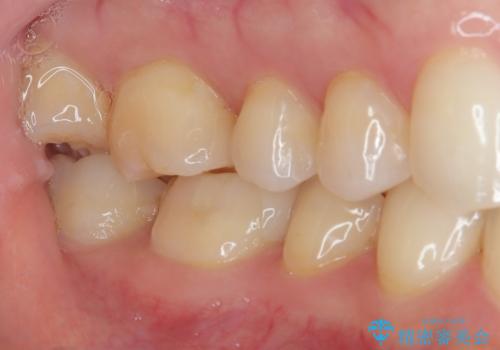

歯と歯茎の間に圧排糸と言われる糸を入れてシリコーン印象材にて精密な型どりをしました。

セラミックインレーの装着時には、唾液の侵入を防ぐために、ラバーダム防湿を行いました。

見た目、機能面共に大変喜んでいただきました。